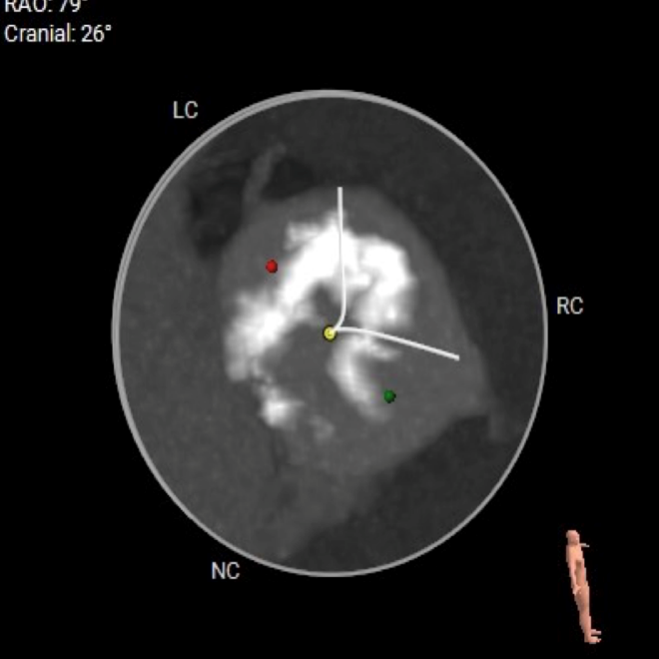

CT数据显示该患者为Type0主动脉瓣。

主动脉瓣瓣环周长97.1mm,平均周长径 30.9mm,SOV:34.8mm*47.5.3mm*42.4mm,瓣叶增厚,瓣上钙化分布不均,瓣环水平夹角66°。

冠脉高度测量

左冠开口高度20.4mm

右冠开口高18.8mm

钙化分布:HU850钙化积分881mm³